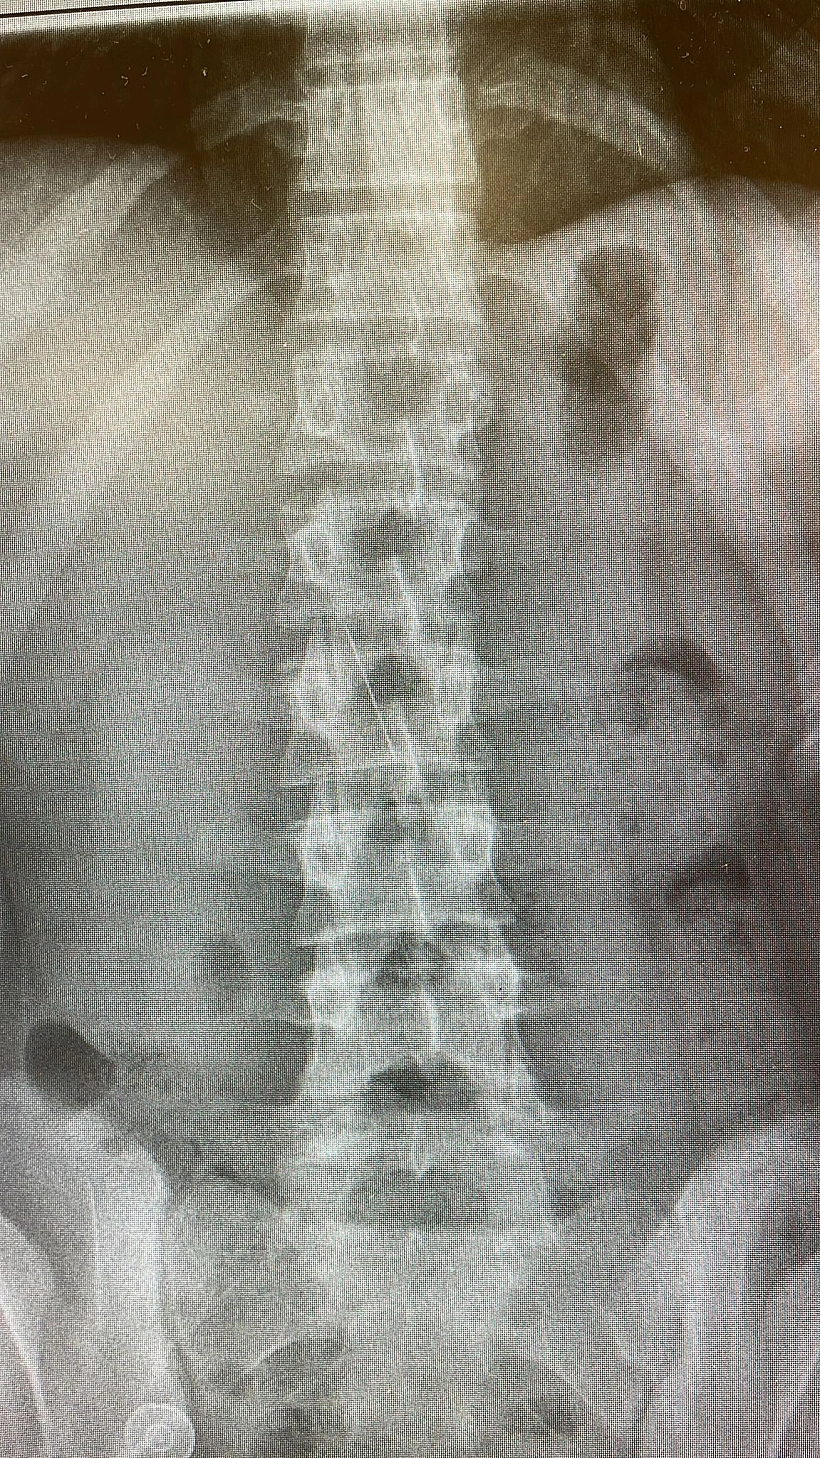

הנערה הבינה כי דרושה התערבות, ובהתייעצות עם רופא הופנתה לבית חולים שערי צדק, שם עברה בדיקות וצילומים, והוכנסה לפרוצדורה רפואית לחילוץ הסיכה מגופה. הסיכה הייתה נעוצה לכל אורכה, בעומק 4 ס"מ בתוך בטנה, ויצרה חור בדופן הקיבה - שהביא לזיהום בבטן.